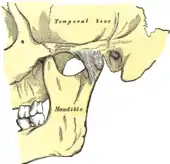

Temporomandibular joint

Left temporomandibular joint, lateral view.

The temporomandibular joints are the dual articulation of the mandible with the skull. Each TMJ is classed as a "ginglymoarthrodial" joint since it is both a ginglymus (hinging joint) and an arthrodial (sliding) joint,[41] and involves the condylar process of the mandible below, and the articular fossa (or glenoid fossa) of the temporal bone above. Between these articular surfaces is the articular disc (or meniscus), which is a biconcave, transversely oval disc composed of dense fibrous connective tissue. Each TMJ is covered by a fibrous capsule. There are tight fibers connecting the mandible to the disc, and loose fibers which connect the disc to the temporal bone, meaning there are in effect 2 joint capsules, creating an upper joint space and a lower joint space, with the articular disc in between. The synovial membrane of the TMJ lines the inside of the fibrous capsule apart from the articular surfaces and the disc. This membrane secretes synovial fluid, which is both a lubricant to fill the joint spaces, and a means to convey nutrients to the tissues inside the joint. Behind the disc is loose vascular tissue termed the "bilaminar region" which serves as a posterior attachment for the disc and also fills with blood to fill the space created when the head of the condyle translates down the articular eminence.[42] Due to its concave shape, sometimes the articular disc is described as having an anterior band, intermediate zone and a posterior band.[43] When the mouth is opened, the initial movement of the mandibular condyle is rotational, and this involves mainly the lower joint space, and when the mouth is opened further, the movement of the condyle is translational, involving mainly the upper joint space.[44] This translation movement is achieved by the condylar head sliding down the articular eminence, which constitutes the front border of the articular fossa.[35] The function of the articular eminence is to limit the forwards movement of the condyle.[35] The ligament directly associated with the TMJ is the temporomandibular ligament, also termed the lateral ligament, which really is a thickening of the lateral aspect of the fibrous capsule.[35] The stylomandibular ligament and the sphenomandibular ligament are not directly associated with the joint capsule. Together, these ligaments act to restrict the extreme movements of the joint.[45]